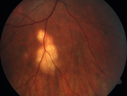

31 year old man with vision loss in the right eye more than the left eye. He has an anaplastic astrocytoma diagnosed 10/2017 the first one was 10/2014. These are different locations. They are treating them with Chemotherapy and Avastin. It might be that one might have spread from the other. He was clean for 3 years. He is on Avastin and Temozolomide but his blood counts have been good. December 2017 he had a herpes superficial infection in the right eye which responded to treatment. The last neurosurgery was October 2017. Going to Duke June 5 and seeing a neuroophthalmologist there. VA OD: Dcc20/40 PH20/25 NccJ5 VA OS: Dcc20/16 PH20/10 NccJ1+ His fundus is presumably nocardia, pneumocystis, aspergillis or cryptococcus. His LP was negative and he was tried on a course of antifungals. He was then lost to followup

Multifocal Choroiditis - Pneumocystis - aspergillis - cryptococcus606 views31 year old male with anaplastic astrocytoma on chemotherapy with mild vision loss in the right eye. LP did not reveal organism. He was placed on a trial of anti-fungal medications and lost to follow-up00000